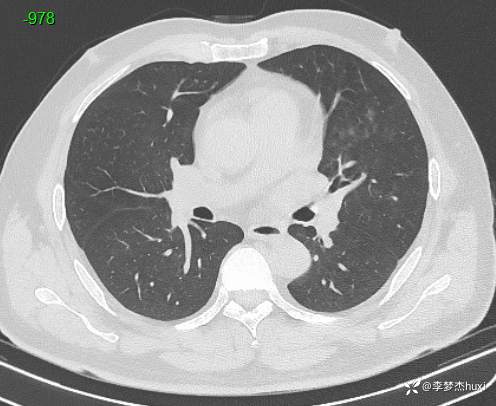

男性48岁,咯血3小时,咯血病因?

主诉:咯血3小时

简要病史:患者于入院前3小时无明显诱因出现咯血,为鲜红色,量较多,约10ml,伴胸闷、压气,伴咳嗽,无明显咳痰。

体格检查:T36.2℃,P110次/分,R20次/分,BP250/130mmHg。神清,呼吸平稳,浅表淋巴结不大,双肺叩清音,双肺未闻及干湿性啰音,心率110次/分,律齐,无杂音。腹部平坦,软,全腹无压痛,无反跳痛及肌紧张,肝脾肋下未触及,双下肢无水肿。

辅助检查:胸部CT:双肺炎症,双肺纹理增多,主动脉及冠状动脉钙化,主肺动脉稍增粗,右侧肾上腺点状高密度影,考虑脂肪肝。

临床诊断:肺炎咯血